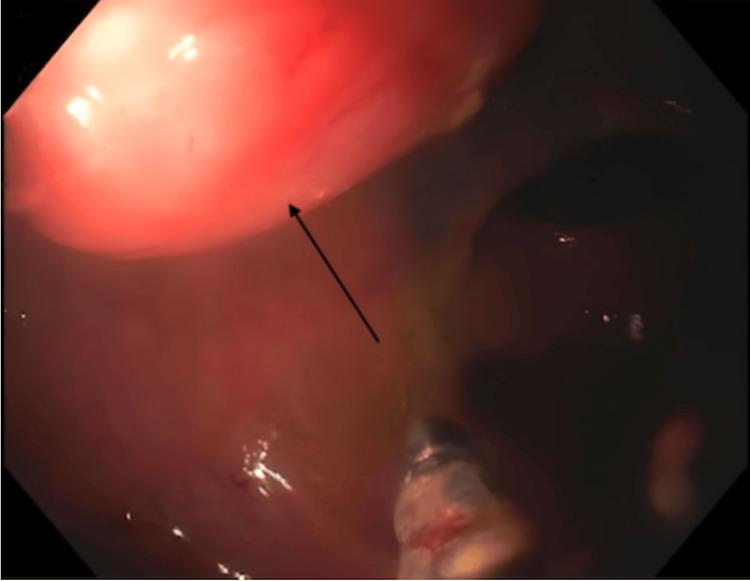

A woman in her 60s with a past medical history of recurrent  (. ) presented for surgical consultation after a colonoscopy revealed a mass in the rectum. Preoperative biopsy revealed mucosal excrescence with no dysplasia or malignant changes. The final pathology showed a solid, submucosal rectal mass that was positive for SOX10 and S100 on immunohistochemistry, supporting our diagnosis of Schwannoma. This case emphasizes the importance of considering schwannomas in the differential diagnosis of patients presenting with a rectal mass no matter how rare it may be.

一名60多岁女性,既往有复发性(.)病史,结肠镜检查发现直肠肿物后前来接受外科会诊。术前活检显示黏膜赘生物,无发育异常或恶性改变。最终病理显示为实性、黏膜下直肠肿物,免疫组化SOX10和S100呈阳性,支持我们对神经鞘瘤的诊断。该病例强调了在直肠肿物患者的鉴别诊断中考虑神经鞘瘤的重要性,无论其多么罕见。